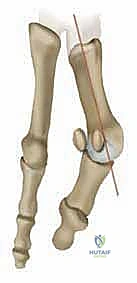

* انحراف العظمة المشطية الأولى: تبدأ العظمة المشطية الأولى (العظمة الطويلة التي تسبق الإبهام) بالانحراف نحو الداخل (باتجاه القدم الأخرى).

* انحراف السلامية (الإبهام): كرد فعل، ينحرف إصبع الإبهام نفسه نحو الخارج (باتجاه الأصابع الصغيرة للقدم).

* بروز المفصل: هذا الانحراف المتعاكس يؤدي إلى بروز رأس العظمة المشطية الأولى، مكوناً الكتلة العظمية المؤلمة التي نراها من الخارج.

* الزاوية المفصلية المشطية البعيدة (DMAA): في الحالات المتقدمة، يتشوه سطح المفصل نفسه ويميل بزاوية غير طبيعية. الجراحات التقليدية تفشل في علاج هذه الزاوية، وهنا تبرز أهمية تقنية شفرون ثنائية المستوى التي يطبقها الدكتور هطيف لتصحيح هذه الزاوية بدقة متناهية.